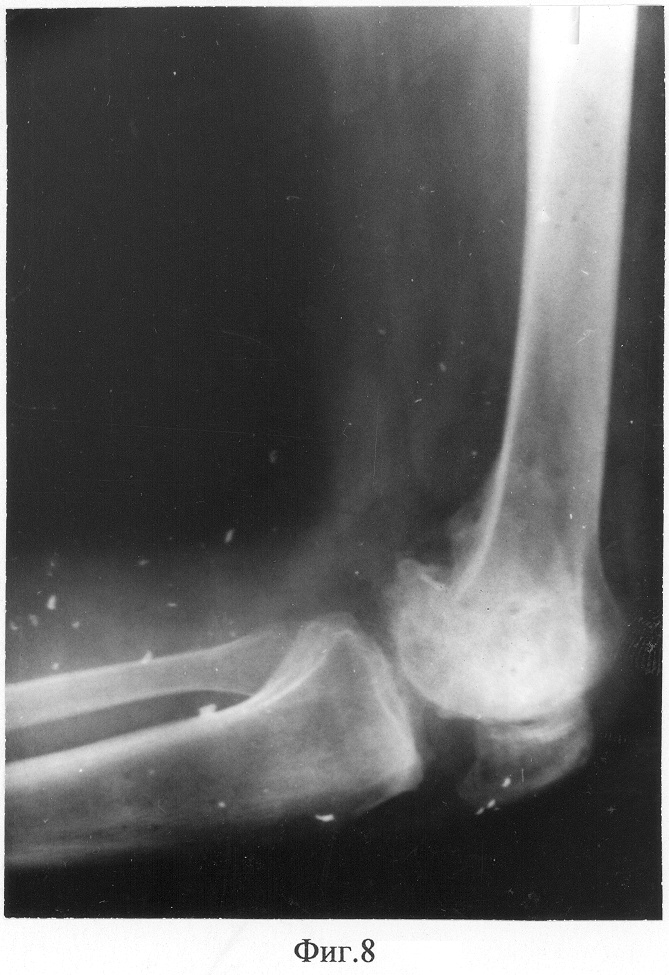

Фиг.8 – рентгенограмма коленного сустава пациента в боковой проекции с максимальным сгибанием через 1 год после снятия аппарата.

Достигнуто сращение мыщелка бедренной кости с восстановлением артикулирующих поверхностей коленного сустава и биомеханической оси конечности (Фиг.7, 8). Длина ног одинаковая. Ходит не хромая, боли отсутствуют, устойчивость голени полная. Объем движений в коленном суставе перераспределен в функционально выгодный диапазон (100°-180°).